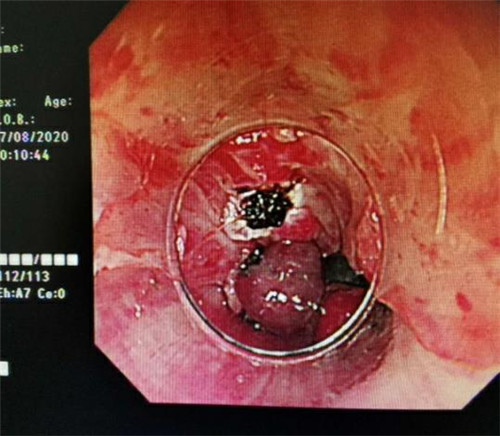

手术中,在镜下发现数条食管静脉曲张延伸至胃底,胃腔内有大量新鲜红色血液及血凝块,寻找到出血部位时仍在向外渗血,血压持续下降,患者时刻有生命危险。曹鹏副主任当机立断对曲张静脉破口处进行组织粘合剂及硬化剂注射,并对曲张静脉进行套扎治疗,在麻醉师陈琦的保驾护航下,整个过程不到半个小时,为患者成功止血,患者转危为安。